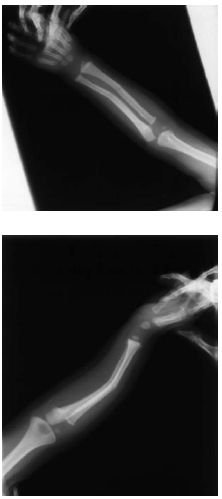

Observe as imagens das radiografias.

O periósteo mais espesso e mais elástico e a cortical óssea altamente porosa e vascular, associados a maior quantidade proporcional de matriz protéica em relação ao seu conteúdo mineral, torna a constituição óssea mais maleável, justificando a ocorrência de: